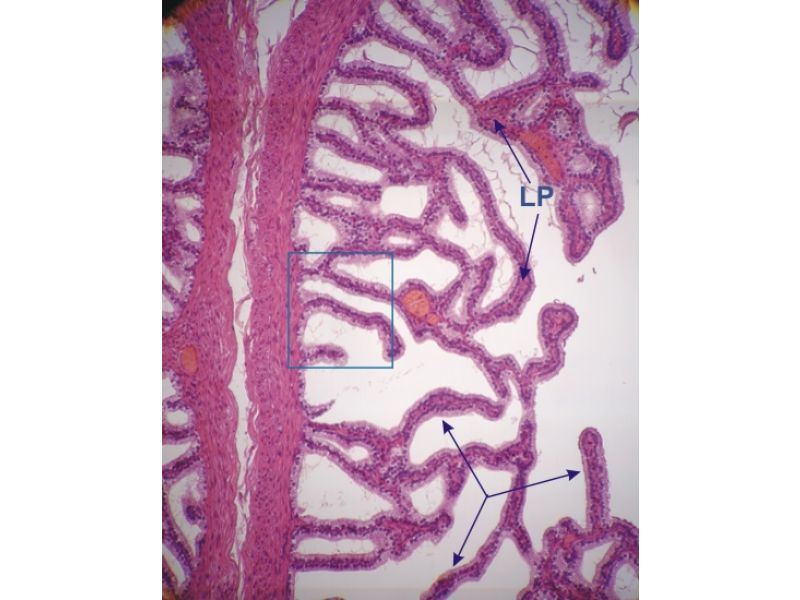

Vesicula seminalis

Slide 81Vesicula seminalis

- Mucosa

- Epithelium

- Lamina propria

- Muscle layer

Mucosa

- Lumen

- Irregular

- Store secretions

- Pseudostratified columnar epithelium

- Lamina propria

- Contains AVL

- Folded mucosa ^^ surface area

Muscle layer

- Inner circular

- Outer longitudinal